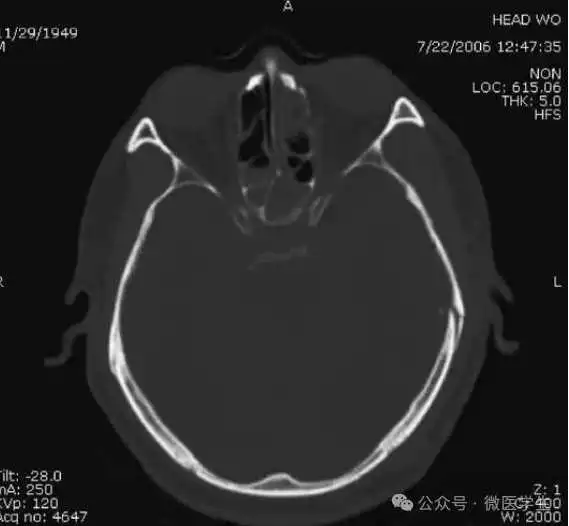

颅脑CT常用的三个窗(图A-C):

- 图A:骨窗(the bone window)

图A:骨窗;主要用于明确骨折、窦腔病变、颅内积气。

本例表现:骨窗示:右顶骨骨折;三个窗均示:软组织水肿并皮下积气;血窗:少量硬膜下血肿。